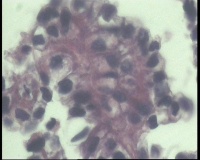

| 一般病史 | 彩超:盆腔可见囊实性回声,囊性为主,大小约5.0x3.7厘米,其内可见分隔回声,部分分隔内回声不纯净,形态欠规整 | ||||

| 标本名称 | 腔镜下右侧卵巢囊肿手术 | ||||

| 大体所见 | 囊壁样组织5.5x5.0厘米,4.5x2.5厘米2块,壁厚0.1-0.2lm,囊壁大部分光滑,局灶见0.7x0.5x0.3厘米淡黄色突起组织,另见淡黄色、肉粉色质软组织2.8厘米一堆。 | ||||